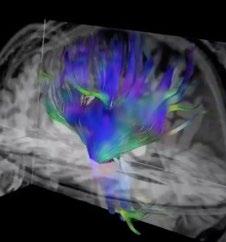

ISMRM: MRI detects brain changes in past cannabis users

If you’ve been following cannabis use and cannabis use disorder, you might not be surprised to learn that our most read story was about the heavy use of cannabis and its effect on the brain as detected by MRI. New Zealand researchers reported that heavy cannabis use is associated with structural brain changes

such as volumetric differences in subregions of the hippocampus and amygdala.